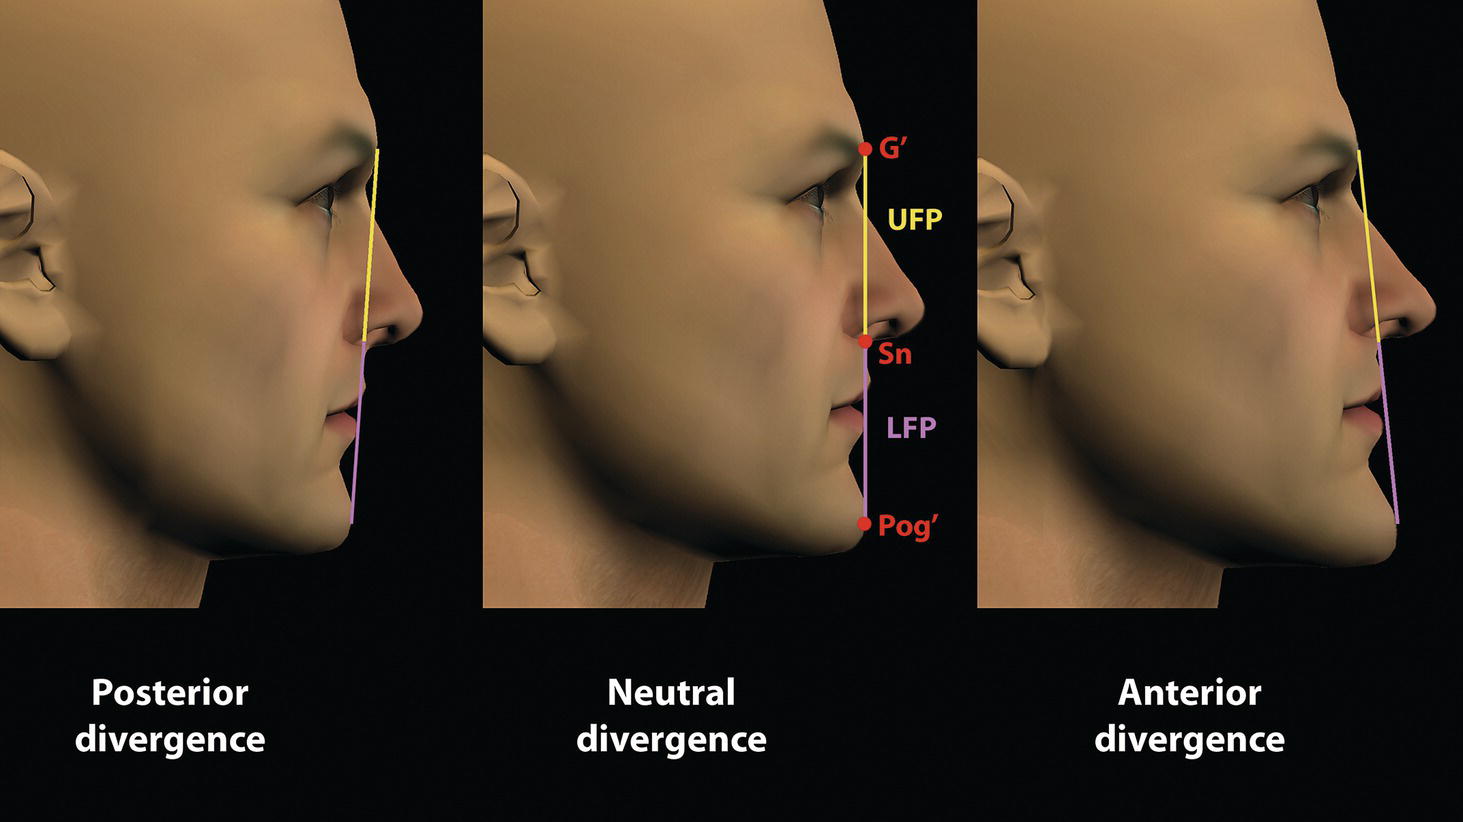

‘It is the common wonder of all men, how among so many millions of faces, there should be none alike’. Sir Thomas Browne (1605–82), English physician and writer, Religio Medici (1643)1 Individual variability is a fundamental principle in human biology. One of the most variable and distinguishable parts of the human body is the craniofacial complex. Clinicians will often compare a patient’s craniofacial measurements and proportions to the so‐called population norms (normative values) or even to classical ideals. However, Simon (1926) stated: ‘all we ever find are variations; an exact, ideal normal does not exist, cannot exist. And this is our enigma; in theory we will never find the normal, in practice we forever feel its need and apply it constantly’.2 The use of population norms may be logically enhanced by evaluating normal ranges of variability. Therefore, clinicians must have a thorough understanding of the normal ranges of variability in every aspect of craniofacial form, depending on age, sex and ethnic variability. Developmental disorders, as well as traumatic injuries and pathological conditions, may lead to deformities of the head and the face. Therefore, clinicians need to have a thorough understanding of the normal anatomy and morphological range of variation of the craniofacial complex in both males and females of different ages and ethnic groups, to act as guidelines when treatment planning the restoration of normal craniofacial proportions. Classifications that are useful for descriptive purposes include: A proportion index provides a numerical expression of the proportionality of a region of the craniofacial complex. The use of proportion indices dates back through the history of craniometry, particularly in the late nineteenth century. Linear (chord) or surface (arc) distances of the skull were measured between a variety of defined craniofacial landmarks; with any two measurements, the smaller was expressed as a percentage of the larger in order to provide a proportion index value. These could be used to provide an indication of skull shape. Figure 8.1 Determination of the normality or abnormality of any craniofacial measurement (or proportion index value) obtained from patients may be evaluated by comparison with the normative values obtained from a normal (average representative) population sample. The normal range of measurements is provided by the mean ±2 standard deviations (SD). The shape of the normal distribution curve shown is determined by the population standard deviation. Craniofacial parameters with small SDs have narrow, taller curves and those with large SDs have broader, flatter curves. Approximately 68% of all values fall within the range of ±1 SD from the mean and 95% within the range of ±2 SD from the mean. The normal range of variability for any craniofacial parameter is taken as being equal to the mean ±2 SDs. Greater differences may be perceived as deformities of gradually increasing severity. The leading researcher in the field of craniofacial anthropometry from the mid‐1960s to the early 2000s was Leslie Farkas, from the University of Toronto. Farkas et al. collected a large quantity of highly relevant anthropometric data between 1968 and 1984, from 2564 individuals.3 These data were used to provide 166 individual facial ratios, presented as proportion indices. In the creation of an index, the smaller measurement is multiplied by 100 (numerator) and divided by the larger measurement (denominator). Thus, a proportion index involves two linear craniofacial anthropometric measurements, with the smaller being expressed as a percentage of the larger. Proportion indices permit objective, quantitative assessment of facial morphology and proportions. Farkas3 identified two basic categories of proportion indices: Each proportion index will have a mean index value and a range of variation for a given population group, based on age, sex and ethnicity. The standard deviation (SD) determines the normal (average) range of variability of an index, from 2 SD below to 2 SD above the mean. Index values within this normal range are regarded as variations of normal proportions.4 Measurements within ±1 SD of the mean are regarded as optimal. The relationship between two measurements is disproportionate if the proportion index value is outside the normal range (Figure 8.1).4 For a number of facial parameters, single morphological measurements or proportion index values may have a large SD and, therefore, wide normal ranges of variation; as such, only measurements or proportion index values which differ considerably from the mean of the population will be perceived as deformities. Conversely, other facial parameters may have very small normal ranges of variability, in which case even a small difference from the mean may be perceived as a deformity. The cephalic index (index cephalicus) is a numerical expression of the ratio between the head width (biparietal diameter) and head length (fronto‐occipital diameter) of a living person. The cephalic index (CI) is calculated by the formula (Figure 8.2): Figure 8.2 Cephalic index. Where: The cephalic index is used in anthropometry to classify head types as (Table 8.1; Figure 8.3): Table 8.1 Classification of anatomical head types Index values according to Martin and Saller.5 Figure 8.3 Head types. The highest cephalic index values occur in the Chinese and the lowest values in African Americans. The larger index values of the Chinese differ significantly from those of whites or blacks (Table 8.2).6 A comparison of the cephalic index values of three ethnic groups was undertaken; North American Caucasians, northern European (German) and eastern European (Czech). The index values indicated a mesocephalic head type for both sexes of North American Caucasians and northern Europeans; and a brachycephalic (short‐wide) head type for the eastern Europeans.6 The head circumference is measured in the horizontal plane around the head, through the glabella and opisthocranion. However, it may be measured across ophyron (the point ‘On’, in the mid‐sagittal plane, of a line tangent to the upper limits of the eyebrows) rather than glabella in order to eliminate the effect of development of the frontal sinuses and superior orbital rims on head circumference.5,7 African Americans have the largest and the Chinese have the smallest head circumference for both sexes. The head circumference is slightly larger for blacks than for whites for both sexes.6 The initial step in facial analysis involves the examination of the face in frontal view in order to assess the overall facial shape. The variety of facial shapes is almost limitless. However, a simple assessment will allow an overall categorization of the basic facial shape. The basic facial shape in frontal view may be any combination of the following: Table 8.2 Cephalic index of three ethnic groups Data modified from Farkas.6 SD = standard deviation. Table 8.3 Head circumference of three ethnic groups Data modified from Farkas.6 SD, standard deviation. Figure 8.4 Facial height‐to‐width ratios. Variations in facial height and width result in an innumerable variety of the three basic facial shapes (round, square and triangular). For example, an oval facial type is a combination of an overall round face combined with increased vertical facial height and/or reduced facial width. The relationship of vertical facial height to facial width is an important indicator of overall facial shape. There are three methods of evaluating the vertical facial height‐to‐width proportion. These may be presented as proportions, percentages or indices: The facial index (index facialis or index of the morphological face height) is a numerical expression of the ratio between the facial height (nasion to menton) and the bizygomatic facial width (zygion to zygion) of a living person. The facial index (FI) is calculated by the formula: Where: The facial index is used in anthropometry to classify faces as (Table 8.4; Figure 8.6): Figure 8.5 Facial types according to Albrecht Dürer. (Modified from Dürer, 15288.) Figure 8.6 Facial types. Table 8.4 Classification of anatomical face types Index values: male according to Garson, 1885;9 and female according to Martin and Saller, 1957.5 The term facial divergence was introduced by the orthodontist‐anthropologist Milo Hellman,10 although the concept had been described by Albrecht Dürer (1528) (Figure 8.7).8 It is essentially a description of the slope or inclination of the face in the sagittal plane (Figure 8.8). It is determined by the sagittal position of soft tissue pogonion (Pog’) and subnasale (Sn) relative to a vertical line dropped from glabella (G’), with the subject’s head in natural head position. The factor that discriminates and distinguishes facial divergence from profile convexity or concavity is the sagittal position of subnasale (Sn) relative to the G’‐Pog’ line. In order for the face to diverge anteriorly or posteriorly, yet not to exhibit signs of convexity or concavity, subnasale (Sn) must be on or nearly on the G’‐Pog’ line; i.e. the upper facial plane (UFP, G′‐Sn) and the lower facial plane (LFP, Sn‐Pog’) are in a straight line, but diverge anteriorly or posteriorly. Figure 8.7 Facial divergence according to Albrecht Dürer. (Modified from Dürer, 15288.) Figure 8.8 Facial divergence. Anthropometric data from North American Caucasian males and females with untreated Class I dental occlusions describing normal facial divergence and ranges of variability has been provided.11 Mean values of facial divergence are negative, with the faces being slightly posteriorly divergent. Anterior divergence does not occur until two standard deviations from the mean. Facial divergence is essentially an ethnic variation in facial profile form. With a straight profile, i.e. no excessive profile convexity or concavity, anterior or posterior facial divergence is compatible with a normal maxillo‐mandibular and dental occlusal relationship. Figure 8.9 Facial profile contour according to Albrecht Dürer. (Modified from Dürer, 15288.) Figure 8.10 Facial profile contours. The contour of the facial profile may be described as convex, straight or concave. This concept was described by Albrecht Dürer (1528) (Figure 8.9).8 With the patient in NHP, the overall contour of the facial profile may be described by the relationship between two lines: the upper facial plane (UFP), connecting glabella (G’) to subnasale (Sn), and the lower facial plane (LFP), connecting subnasale to soft tissue pogonion (Pog’). In a straight profile, these two lines form a nearly straight line. Such a facial profile is termed orthognathic (Greek orthos: correct or straight; gnathos: jaw). An angle between these two lines indicates facial profile convexity (pogonion behind relative to subnasale in the sagittal plane), or facial profile concavity (pogonion ahead relative to subnasale in the sagittal plane). A convex profile indicates a skeletal Class II jaw relationship (and/or sagittal chin deficiency), and a concave profile indicates a skeletal Class III jaw relationship (and/or sagittal chin excess). However, profile convexity or concavity does not of itself indicate whether the maxilla or mandible/chin is at fault (Figure 8.10). Legan and Burstone12 described the angle of facial convexity for the soft tissue profile. It is formed by the two intersecting lines, the UFP (G′‐Sn) and the LFP (Sn‐Pog′). The mean value is estimated to be 12° ± 4°. An increase in the angle in a clockwise direction is positive; anticlockwise is negative. A high positive value suggests facial profile convexity and a Class II skeletal jaw relationship; a smaller positive value, or a negative value, suggests facial profile concavity and a Class III skeletal jaw relationship. However, the value of this angle does not reveal whether the maxilla or mandible/chin is responsible for the sagittal jaw discrepancy. Figure 8.11 Angle of facial profile convexity (facial contour angle). Downs13 described the angle of convexity, formed by the intersection of line nasion to point A (NA) and line point A to pogonion (A‐Pog). Superior extension of the A‐Pog line forms an angle with the NA line; if behind the NA line, the angle is read as positive, indicating a Class II (convex) skeletal profile. A negative angle of convexity indicates a Class III (concave) skeletal profile. Downs provided a range of values from −8.5° to 10°, with a mean of 0°. Again, as with the facial contour angle, the angle of convexity does not determine the localization of the deformity to the maxilla or mandible/chin. An investigation was carried out with the objective of assessing how lower facial profile convexity influences perceived attractiveness. The lower facial profile of an idealized image was altered incrementally between 14° and −16°, creating a range of images which were evaluated by pretreatment orthognathic surgery patients, laypeople and clinicians. A straight profile was perceived as most attractive and greater degrees of convexity or concavity deemed progressively less attractive, but a range of 10° to −12° was deemed acceptable; beyond these values surgical correction was desired. Patients were most critical, and clinicians were more critical than laypeople.14 The facial angle indicates the relative sagittal prominence of soft tissue pogonion. It is formed by the intersection of the true horizontal plane (or Frankfort Horizontal plane) with a facial vertical plane (N′‐Pog’). The angle should be approximately 90°–92°. A greater angle indicates prominence of soft tissue pogonion; an angle less than 90° indicates retrusion of soft tissue pogonion. The soft tissue facial angle does not of itself determine the aetiology of the sagittal position of soft tissue pogonion, which may be due to one or a combination of: Consequently, the facial angle must be used in conjunction with other measurements and analyses. In addition, when constructing the facial vertical line (N’‐Pog’), if the sagittal position of nasion is not acceptable, it may be adjusted to a more ideal position. The alternative is to use soft tissue glabella (G’) rather than nasion. Downs13 described the facial angle as the inferior inside angle in which the facial line (N‐Pog) intersects the Frankfort Horizontal plane. Downs found a mean value of 88° with a range of 82°–95°. It indicates the relative sagittal position of the mandible/chin to the upper face. Figure 8.12 Facial angle. FH, Frankfort Horizontal plane; TrH, true horizontal plane. Figure 8.13 The relationship of the cranial base angle (saddle angle) and anterior cranial base length on the jaw relationship. The relationship of the anterior to the posterior cranial base is of particular importance in the diagnosis of facial profile contour. This relationship depends on the extent of growth at the sphenoethmoidal and spheno‐occipital synchondroses. The cranial base angle (or saddle angle) represents the orientation of the anterior cranial base (SN line) relative to the posterior cranial base (S‐Ba line).15 The average adult values (bearing in mind that there is negligible change in this angle after the age of six years) for the angle N‐S‐Ba are16: As such, the cranial base angle is an important determinant of craniofacial form, as it influences the sagittal position of the face relative to the neurocranium and the sagittal prominence of the mandible relative to the maxilla. A significantly increased cranial base angle contributes to a skeletal Class II jaw relationship, whereas a reduced cranial base angle contributes to a skeletal Class III jaw relationship. If basion is difficult to identify on a lateral cephalometric radiograph, articulare may be used instead, i.e. the posterior cranial base is drawn between sella and articulare. The average adult values for the angle N‐S‐Ar are16: The anterior cranial base length, measured from sella to nasion, may also influence the jaw relationship. For example, increased anterior cranial base length may lead to a Class II jaw relationship, with the maxilla ahead of the mandible in the sagittal plane, whereas reduced cranial base length may lead to a Class III jaw relationship, with the maxilla behind the mandible in the sagittal plane. The average adult values for the anterior cranial base length are16: Figure 8.14 Parasagittal profile contour. An additional and extremely important consideration is the description of the parasagittal profile (Figure 8.14). It is necessary to evaluate the sagittal relationships of the soft tissues from the infraorbital area to the paranasal area to the parasymphyseal area. For example, maxillary hypoplasia may lead to lack of bony support and flattening in the infraorbital region and paranasal hollowing; with a normal parasymphyseal area, this will lead to the appearance of a concave parasagittal profile. The directional pattern of facial growth has a significant effect on facial profile form. Deviations from the normal pattern of jaw growth may be in a predominantly vertical or horizontal direction. Alternative terms are hyperdivergent facial growth pattern (referring to the excessive divergence of the maxillary, occlusal and mandibular planes in relation to each other and to the anterior cranial base).17 Such a pattern of growth leads to a hyperdivergent facial type, alternatively termed a high angle patient (referring to the increased mandibular plane angle), long face deformity or long face syndrome.18 If the hyperdivergent growth is the primary aetiology to an anterior open bite, the terms skeletal open bite or apertognathia (Latin apertus: open; Greek gnathos: jaw) may be used.19,20 The maxilla rotates downward and backward (posterior vertical maxillary excess), as does the mandible during growth. This leads to reduced sagittal projection of the chin. Such a vertical facial growth pattern will tend to be associated with a posterior pattern of mandibular growth rotation. Figure 8.15 Hyperdivergent, ‘high angle’ facial type.

Facial divergence